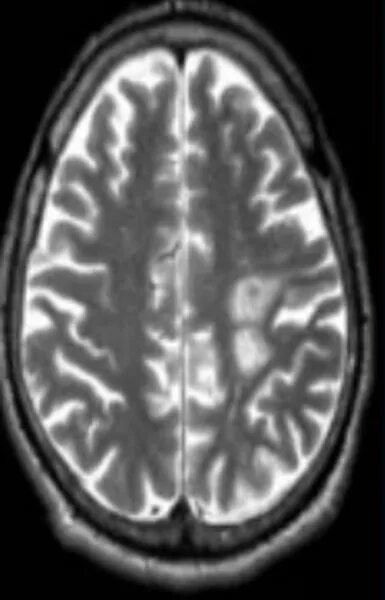

Очаги глиоза сосудистого генеза в головном мозге